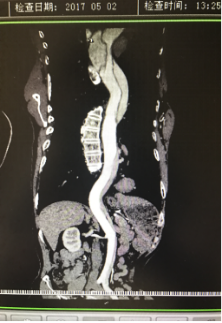

5月2號劉大伯照常早起干活,突然胸部劇烈疼痛,難以忍受,全身大汗,同時伴有右上肢發(fā)涼,他心想這次心絞痛比之前嚴重的多啊,趕緊叫上孩子到吉林國文醫(yī)院心血管內(nèi)科住院,患者長期高血壓病史,血壓一直控制不理想,大夫給他做了檢查,測左上肢血壓:82/45mmHg,右上肢血壓測不出,心率52次/分,右側(cè)肱動脈、尺動脈、橈動脈搏動消失,左側(cè)股動脈搏動較右側(cè)弱?!霸懔耍p側(cè)血壓差別這么大,是不是主動脈夾層了?”,接診大夫趕緊找來李主任,李主任反復詢問患者病情,表情突然凝重起來,患者胸痛這么明顯,血壓低的厲害,主動脈夾層的可能性很大。二話不說,李主任立即聯(lián)系影像科的醫(yī)生準備做主動脈CTA,移動患者做檢查的過程大夫們非常小心,嚴密監(jiān)測患者血壓變化情況。兩個小時后結(jié)果出來了,主動脈夾層從升主動脈一直撕裂到左側(cè)髂總動脈!??!